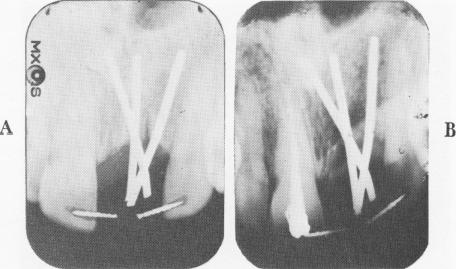

Fig. 8-38. A, Immediate postoperative radiograph. B, A postoperative radiograph taken 21 months later shows very little bone destruction. However, the thickness of the labial and palatal plates of bone camouflages the true picture of the medullary bone.